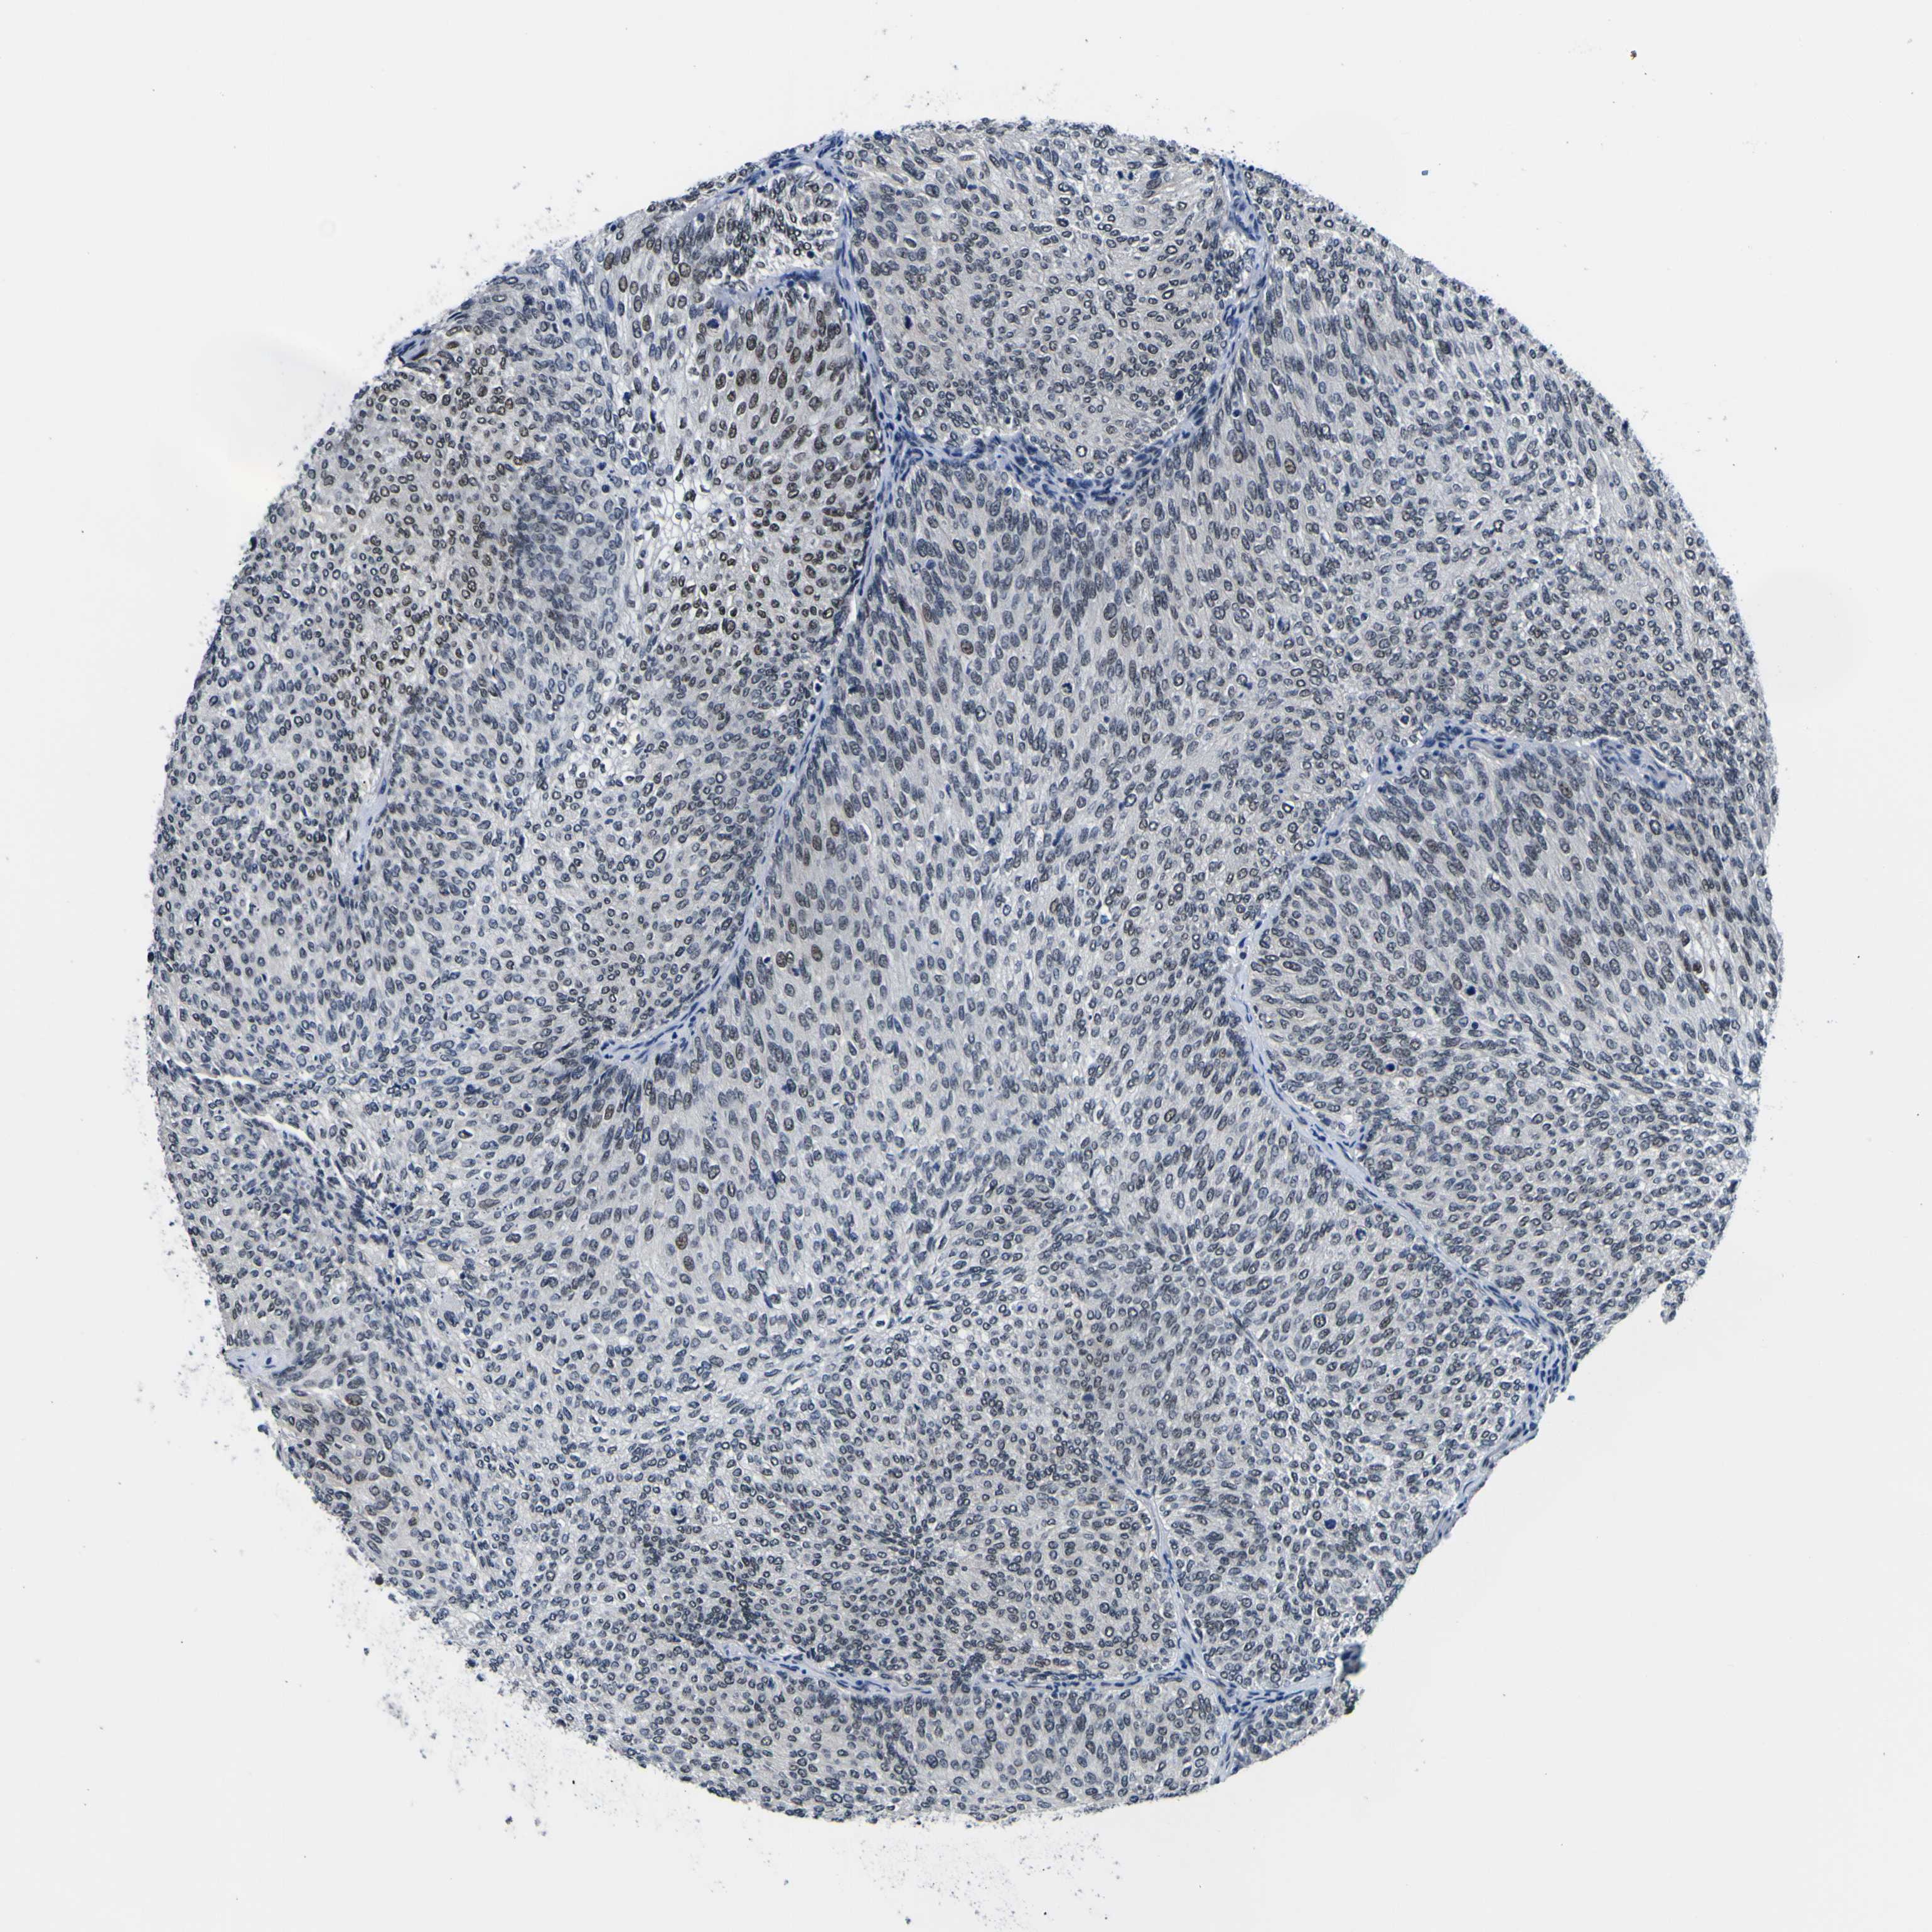

UROTHELIAL CANCER - Protein expressioni

A mouse-over function shows sample information and annotation data. Click on an image to view it in a full screen mode. Samples can be filtered based on level of antibody staining by selecting one or several of the following categories: high, medium, low and not detected. The assay and annotation is described here.

Antibody stainingi

Antibody staining in the annotated cell types in the current human tissue is reported as not detected, low, medium, or high, based on conventional immunohistochemistry profiling in selected tissues. This score is based on the combination of the staining intensity and fraction of stained cells.

Each image is clickable and will lead to virtual microscopy that enables deeper exploration of all samples and also displays staining intensity scores, fraction scores and subcellular localization as well as patient and tissue information for each sample.

Antibody HPA011880

Antibody CAB017786

Urothelial carcinoma, Low grade

Urothelial carcinoma, High grade